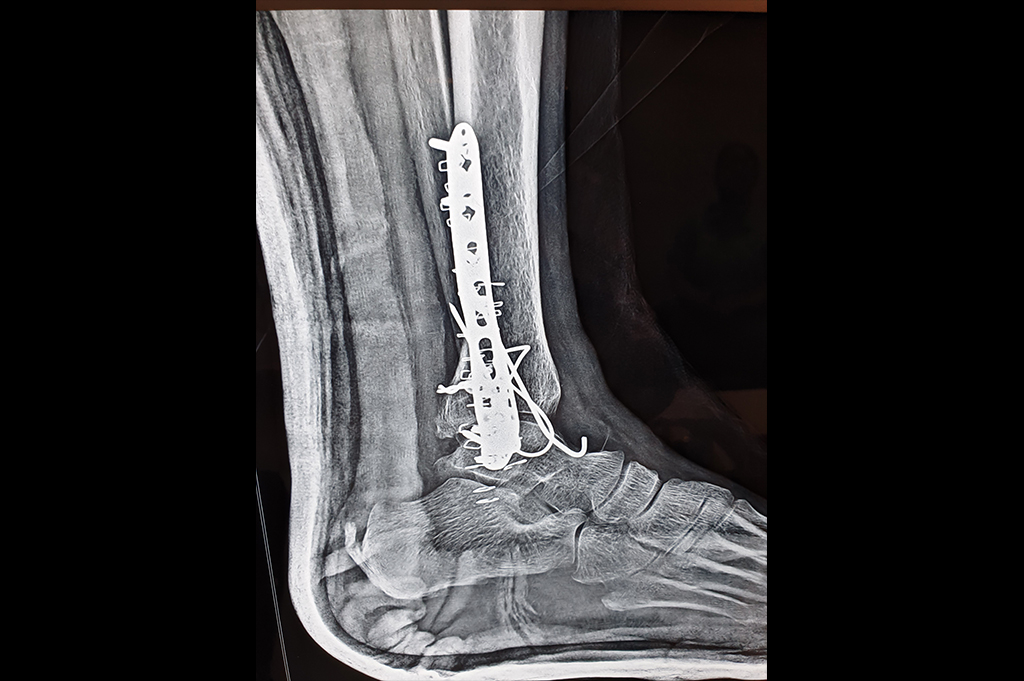

Ankle